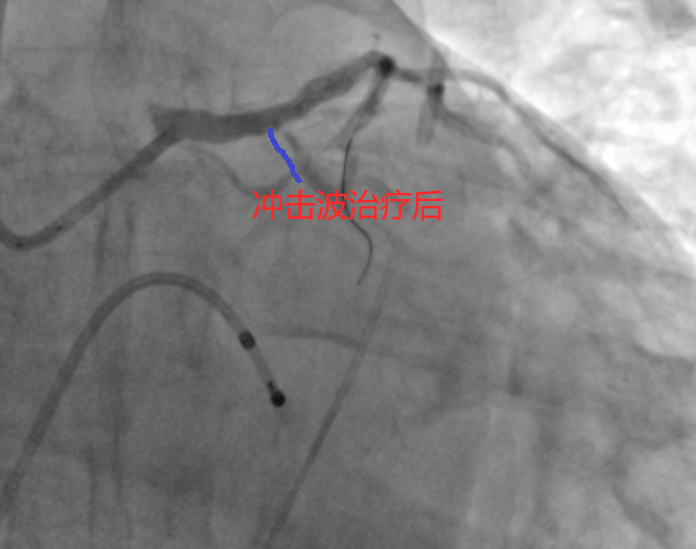

面对患者及其家属再次拒绝冠脉搭桥手术,并强烈要求微创介入治疗,九江学院第二附属医院心血管内科团队进行了缜密的术前讨论。考虑到患者左主干、前降支开口及近段存在重度狭窄且钙化严重,普通球囊扩张可能不能完全预处理狭窄病变,团队最终决定采取冲击波球囊扩张技术。经过充分的术前准备,手术在主动脉球囊反搏(IABP)支持下顺利进行。术中,医生们精准运用3.25X12mm冲击波球囊,在前降支近端及左主干分别进行了数次冲击波治疗,有效处理了钙化病变。最终,成功植入1枚支架,解决了患者的病痛。